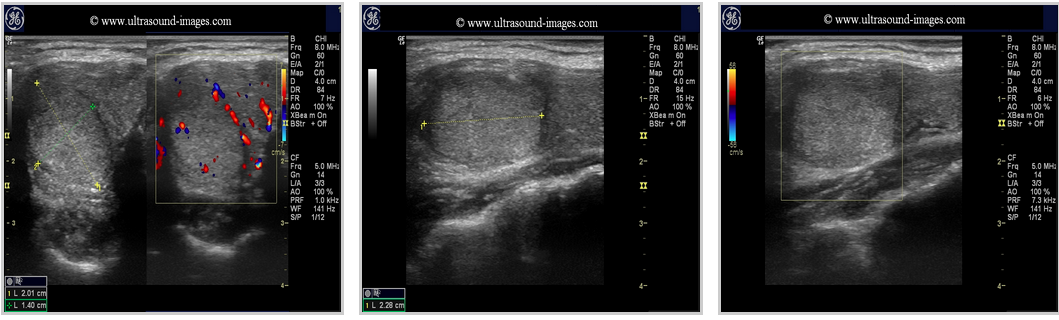

Pics form ultrasound-images.com :

ADENOMAS

thyroid_adenomatous nodules thyroid_follicular adenoma